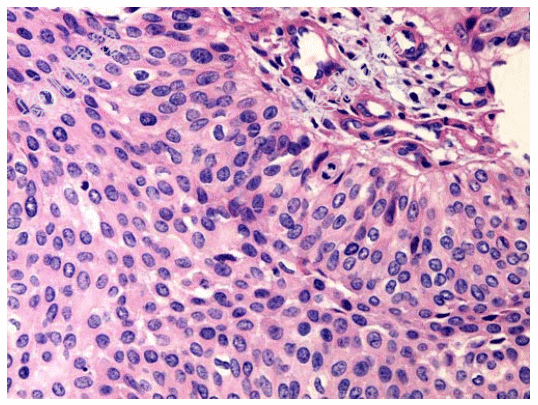

- [材料题] 男性,78岁,血尿2年。CT示右侧肾盂内可见软组织密度影,肾盂肾盏受压变形,考虑为肾脏肿瘤,遂行右肾切除,肾脏大体如图所示,镜检如图所示。临床考虑诊断为右肾盂移行细胞癌Ⅱ级。